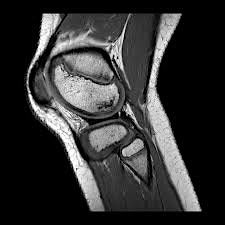

Anatomy of the knee will be detailed using plain film x-ray, MRI and ultrasound imaging, backed up by a practical session in the on-site pro-section lab.

- Recognise normal anatomical appearance of the knee on x-ray and MRI